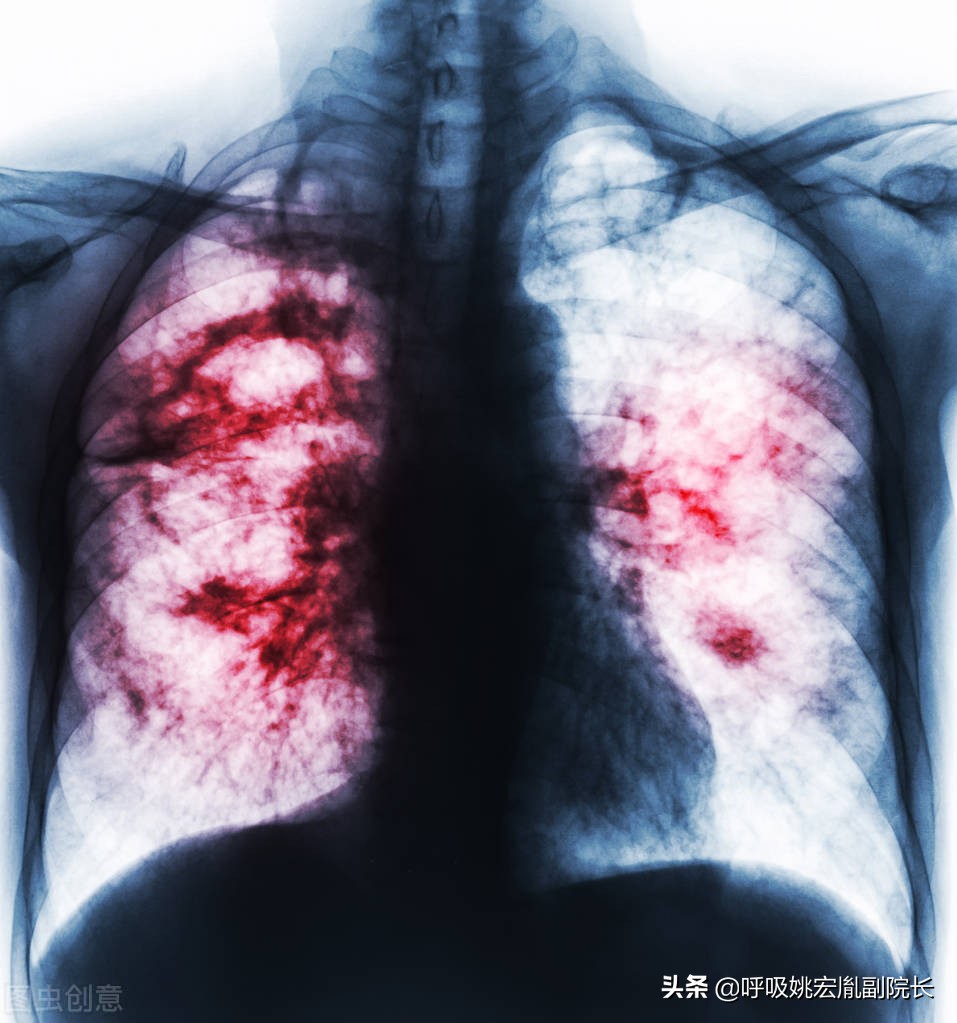

肺炎:老年肺炎常缺乏明显呼吸系症状,症状多不典型,病情进展快,易发生漏诊、错诊。首发症状为呼吸急促及呼吸困难,或有意识障碍、嗜睡、脱水、食欲减退等。

慢阻肺:慢性阻塞性肺病简称慢阻肺,该病是由于一系列的因素(尤其是营养不良,是慢阻肺的“难兄难弟”)导致肺部感染,病情迁延不愈,最终导致慢阻肺,如果没听过慢阻肺,那你一定知道老慢支,慢阻肺就是老慢支的加强版。具有高发病率,高住院率,高死亡率的特点。